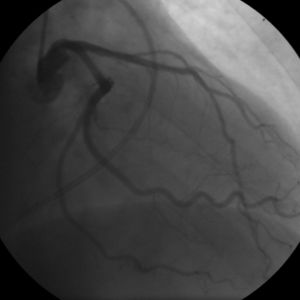

حدد الباحثون بمتشفى كليفلند (Cleveland Clinic) في دراسة تمت سنة 2006،منطقة في كروموسوم 17 مختصة بالعائلات التي تصاب بعدة حالات من الجلطة القلبية(myocardial infarction). كما يوجد خلاف حول العلاقة بين الإصابة بمرض تصلب الأوعية الدموية (atherosclerosis) والعدوى بالبكتيريا Chlamydophila pneumoniae،بينما أُثبت وجود هذه البكتيريا الذي تعيش داخل الخلية في صفيحة الكولسترول لدى المرضى المصابين بتصلب الأوعية، فما زالت هذه البراهين غير حاسمة فيما إن كانت هذه البكتيريا بحد ذاتها عامل مسبب للمرض. لم يظهر العلاج بالمضادات الحيوية (antibiotics) لمرضى تصلب الأوعية الدموية أي تقليل لخطر الإصابة بالنوبة القلبية (heart attacks) أو أمراض الأوعية التاجية الأخرى. منذ سنة 1990 والبحث جاري نحو خيارات جديدة للعلاج لأمراض أوعية القلب التاجية تُركز على استخدام ما يسمى تكوّن الأوعية الدمويةangiogenesis والخلايا الجذعية stem cell. حيث أجريت الكثير من التجارب السريرية إما بتطبيق العلاج ببروتين عامل النمو لتكوّن الأوعية الدموية (angiogenic growth factor) مثل: FGF-1 أو VEGF ،أو العلاج بالخلايا باستخدام أنواع مختلفة من الخلايا الجذعية. وما زالت الأبحاث قائمة توعد بمستقبل مشرق للعلاج خصوصا فيما يتعلق ب FGF-1 والانتفاع الخلايا المُولدّة للخلايا المبطّنة للأوعية الدموية endothelial) progenitor cells).